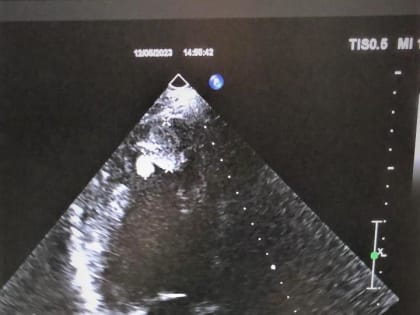

В РОСТОВЕ МОЛОДОЙ ВРАЧ СПАСЛА МУЖЧИНУ ОТ ВНЕЗАПНОЙ СЕРДЕЧНОЙ СМЕРТИ

В Ростове молодой врач отделения ультразвуковой диагностики горбольницы №6 Татьяна Жукова спасла пациента от вероятной внезапной сердечной смерти.

Ростовская область, 17 мая 2023. DON24.RU. В Ростове молодой врач отделения ультразвуковой диагностики горбольницы №6 Татьяна Жукова спасла пациента от вероятной внезапной сердечной смерти.